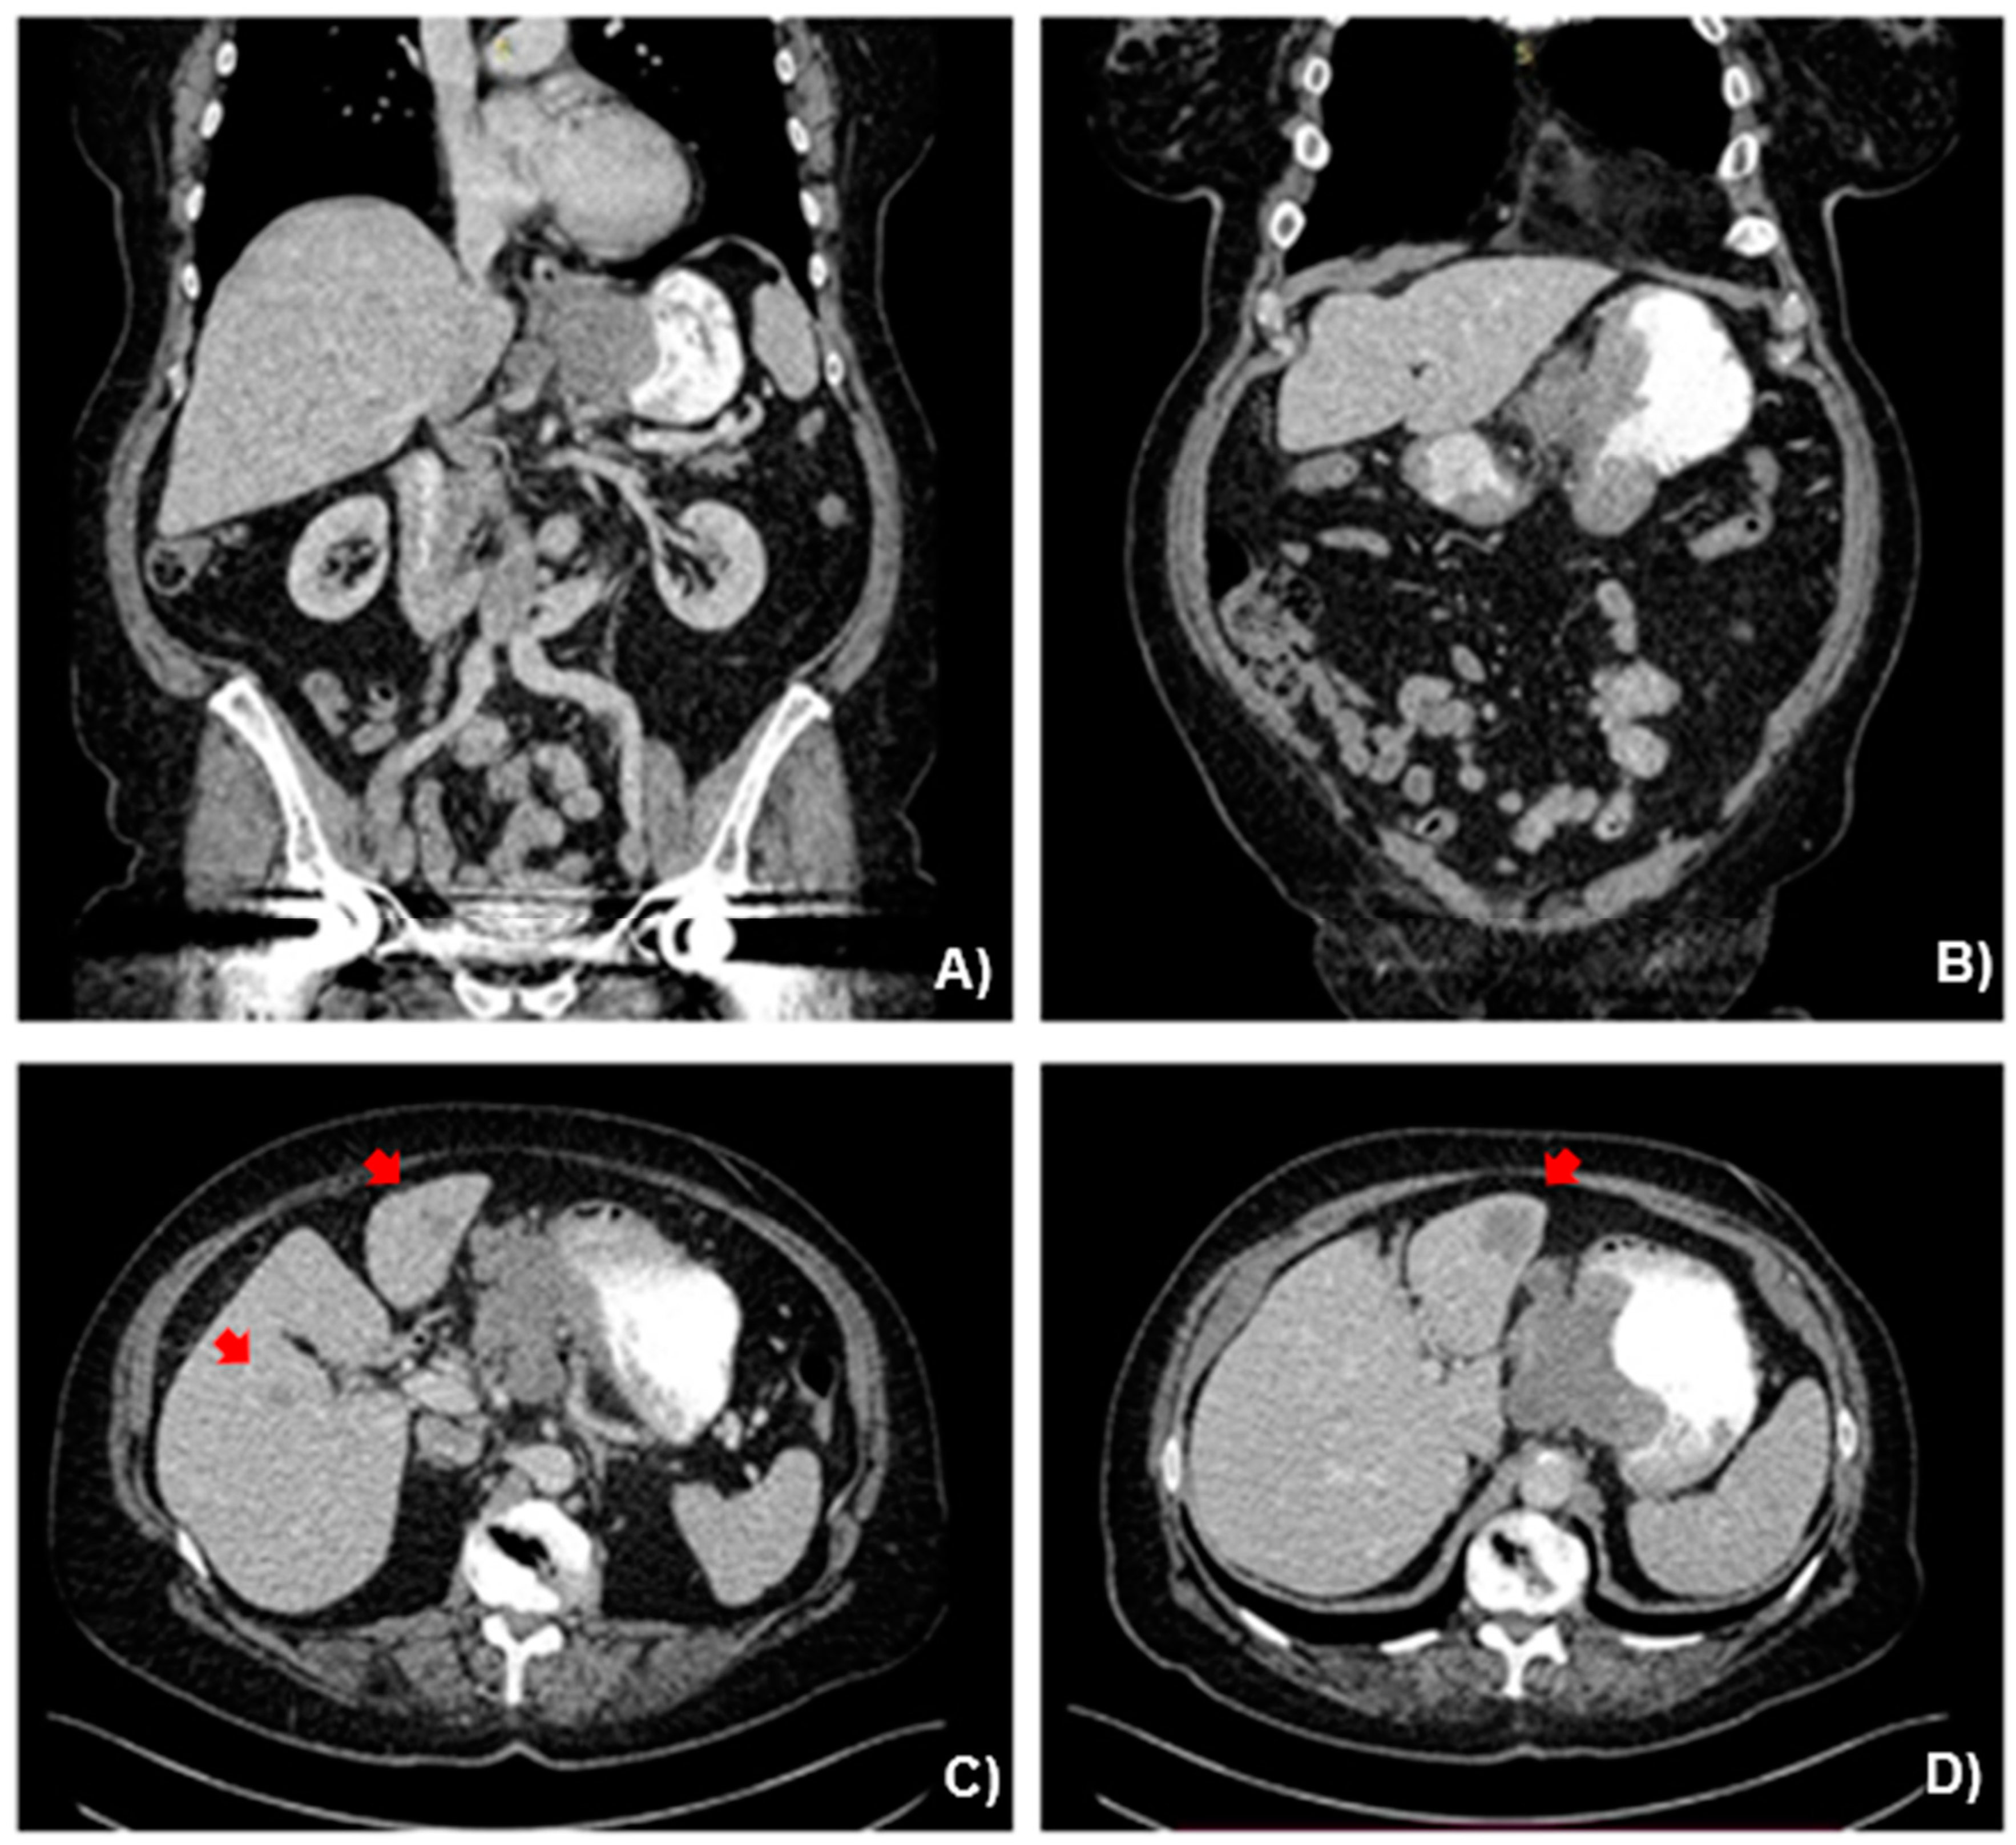

2.2. Case Presentation

3.1. Case Management